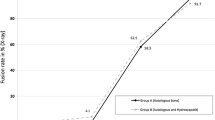

Fusion rates are increased according to the ratio of autograft in all groups: 90.9 % in Group I, 87.8 % in Group II, and 85.7 % in Group III. However, there were no significant differences between groups (p = 0.22). The fusion rates significantly increased as the amount of bone graft increased to over 12 ml, showing 81.5 % in Group A and 92.0 % in Group B (p = 0.03).

The bone fusion rate was 90.9 % in Group I with 100 % autograft, 87.8 % in Group II with over 50 % autograft and 85.7 % in Group III with less than 50 % autograft; however, the differences between groups were not statistically significant (p = 0.22) (Table 4). However, bone fusion exhibited significant differences between graft volume-based groups showing 81.5 % in Group A with less than 12 ml of bone graft and 92.0 % in group B with over 12 ml (p = 0.03) (Table 5).

Simple X-ray images revealed a fusion rate of more than 90 % in the anterior interbody fusion of Riouallon et al. [28] and in the transforaminal lumbar interbody fusion of Zairi et al. [29] over the follow-up period of more than 2 years. According to Park et al. [5], CT revealed a fusion rate of 77.3 % over the follow-up period of more than 2 years on MI-TLIF. Moreover, Thalgott et al. [17] reported that HA is an effective bone graft extender in patients with difficulty achieving bone fusion. The fusion rate was 92.5 % in posterolateral lumbar fusion by adding a 15 cc of HA in each segment to the autobone collected from the iliac bone. To acquire a higher fusion rate in this study, the authors tried to perform bone grafting in a large amount after sufficient corpectomy and interbody distraction intraoperatively. According to the CT results of fusion rate by bone graft volume, a statistically significant difference was shown in volumes of more than 12 cc. To achieve a satisfactory fusion rate of more than 90 %, at least more than 12 cc of bone graft volume is required.